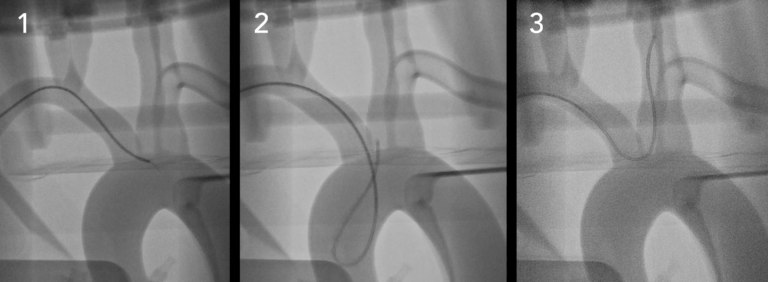

重复模拟具有真正生理功能的血管内病例。?生理和解剖学上准确的人类硅胶血管?在模拟血管内手术时,PRO?可提供的逼真的模拟体验:

●具有清晰视野的多种成像模式– CT,荧光检查和照相机

●执行EVAR,TEVAR,FEVAR,TAVR等